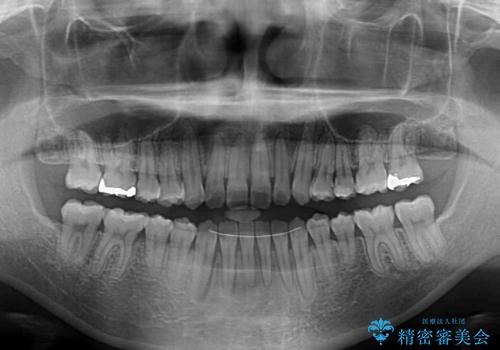

- 前歯の上下スペースと前歯の隙間を気にして来院された患者様です。

インビザラインにより上下の前歯の隙間を閉じていくこととしました。

上下の隙間に舌が入り込むことが、すきっ歯やオープンバイトの原因であったため、舌の筋肉のトレーニングも並行して行い、後戻りの抑制を図りました。